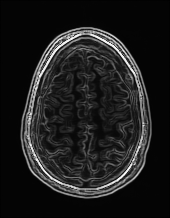

Edge preserving has always been a crucial concern in the design of reconstruction models. To improve the quality of reconstructed images and preserve image edges, some works suggested introducing edge priors in the original restoration problem to preserve image edges [4, 34]. However, they will suffer from complicated algorithm design and time-consuming training processes. Recently, some more efficient methods have been proposed to use edge maps as external guidance for image restoration. For example, Yang et al. [48] used off-the-shelf edge detectors to extract image edges from the degraded images. Fang et al. [12] predicted image edges by constructing an edge reconstruction network. Huang et al. [18] designed a novel dual discriminator GAN framework for solving fast multi-channel MRI, in which one GAN network is built for edge information enhancement. Inspired by these methods, we also consider introducing image edge prior as external guidance to MRI reconstruction since 1) image edges are prominent and distinguishable features in MRI (see Fig. 1), which can serve as a good guide to the model to recover high-frequency details; 2) the ground truth edges can be easily fetched via ordinary edge extraction operators, like Canny, Sobel, and Prewitt, which means that the edge maps can be learned in a data-driven manner. However, how to effectively utilize image edge priors to guide image reconstruction still remains a challenge. In some methods, edge information was simply concatenated with the input image and passed to the next stages. Though this is a simple way to utilize the edge priors, it may not give full play to the guiding role of the edge priors. Therefore, in this work, we want to explore a more efficient and effective mechanism to fully take advantage of image edge priors.

(a)

(b)

(c)

fastMRI is a large-scale MR dataset jointly established by Facebook AI Research and NYU Langone Health. It provides both knee and brain datasets for evaluation. In our work, we use the multi-coil knee dataset, which was acquired on three clinical 3T systems or one clinical 1.5T system using a 15-channel knee coil array. The dataset includes data from two pulse sequences, yielding coronal proton-density weighting with (PDFS) and without (PD) fat suppression. As is shown in Fig. 1, PD images usually contain more structural and prominent edge features than PDFS images, which suggests that it is more challenging to use edge guidance on PDFS datasets. Therefore, we explore the effectiveness of EAMRI on these two modalities. Following [13], for both PD and PDFS knee datasets, we separately filter out 227 volumes (8332 slices) for training and 24 volumes (1665 slices) for testing. The dataset is centrally cropped to .